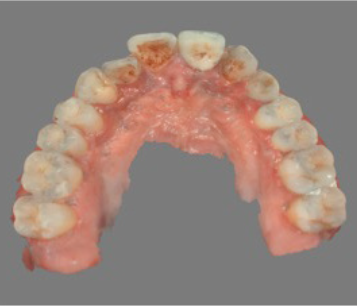

Initial clinical situation showing displaced upper left canine Initial occlusal view of the displaced canine site

Initial situation The upper left canine has drifted into the premolar space following orthodontic treatment. The decision was made to extract and place an implant, driven by the final prosthetic position.